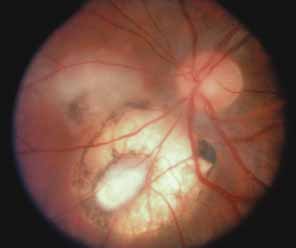

Active retinal involvement in acute toxoplasmosis may be associated with an acute elevation of intraocular pressure, sometimes producing corneal edema. When the cornea is cleared with topical glycerin, the angle is found to be open and a minimal anterior chamber reaction is present. The mechanism of the glaucoma is believed to be immune complex (antigen–antibody) deposition in the trabecular meshwork, rather than obstruction by cellular debris.21 The elevated pressure responds well to timolol or acetazolamide and does not require topical corticosteroids. Systemic treatment of the active retinitis should follow only if the optic nerve (positive Marcus Gunn), macular center, or peripapillary retina is involved. This unique entity will be missed if a fundus examination is not performed in all cases of hypertensive uveitis (Fig. 2).